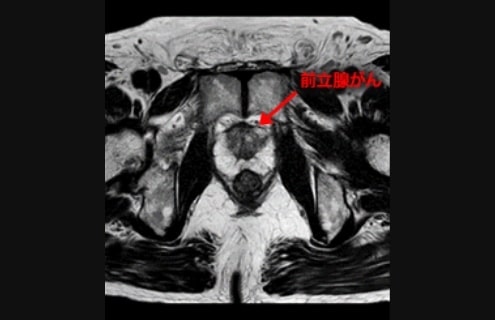

前立腺MRI検査

前立腺がんの疑い症例の局在診断や生検のガイドとしてMRIは有用性を発揮します。

• ※T2強調画像